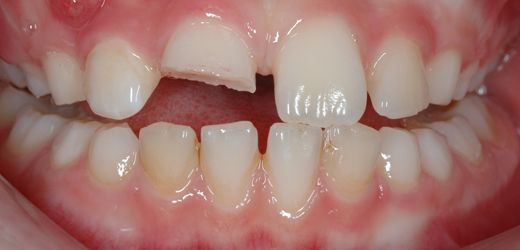

- Εκτεταμένο κάταγμα του δοντιού, με αποτέλεσμα να αποκαλύπτεται ο πολφός (νεύρο). Η αποκάλυψη του πολφού και η έκθεση του μέσα στη στοματική κοιλότητα σημαίνει και τη μόλυνση του, με αποτέλεσμα στη συνέχεια το δόντι να παρουσιάζει έντονη φλεγμονή και να πονάει.

Όσον αφορά την απονεύρωση στα παιδιά τα θεραπευτικά δεδομένα είναι τελείως διαφορετικά. Σύμφωνα με γερμανικά παιδοδοντιατρικά πρωτόκολλα όταν ένα παιδικό δοντάκι είναι βαθιά χαλασμένο πραγματοποιείται η “παιδική απονεύρωση”, η λεγόμενη πολφοτομή, η οποί είναι μία διαδικασία πολύ πιο απλή και ανώδυνη από την αντίστοιχη απονεύρωση των ενηλίκων. (Για περισσότερες πληροφορίες βλέπε Απονεύρωση (πολφοτομή) δοντιού σε παιδιά).